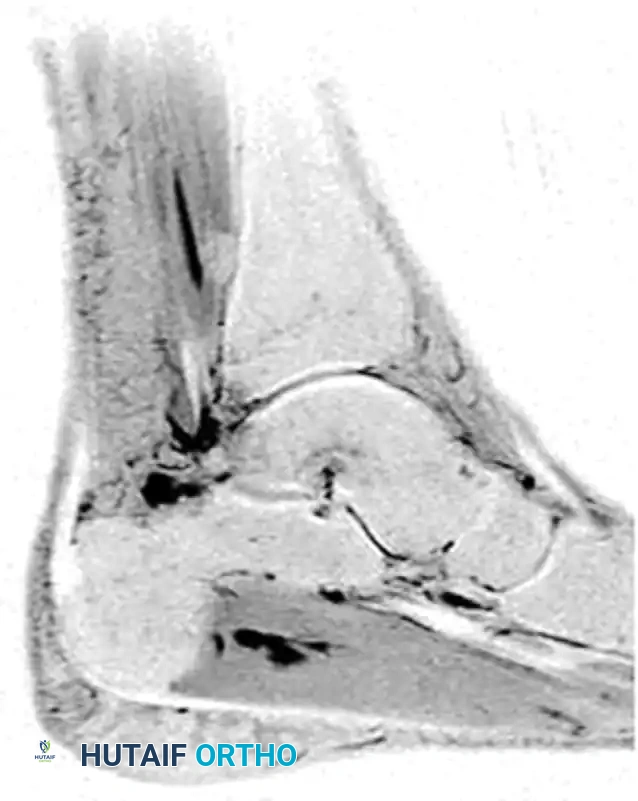

Magnetic Resonance Imaging (MRI) is the gold standard for evaluating the soft tissue integrity of the FHL tendon. MRI effectively delineates tenosynovitis (fluid within the tendon sheath), tendinosis, partial-thickness tears, and the exact location of any intratendinous nodules relative to the fibroosseous tunnel.

MRI of patient with flexor hallicus longus tendinitis with os trigoneum